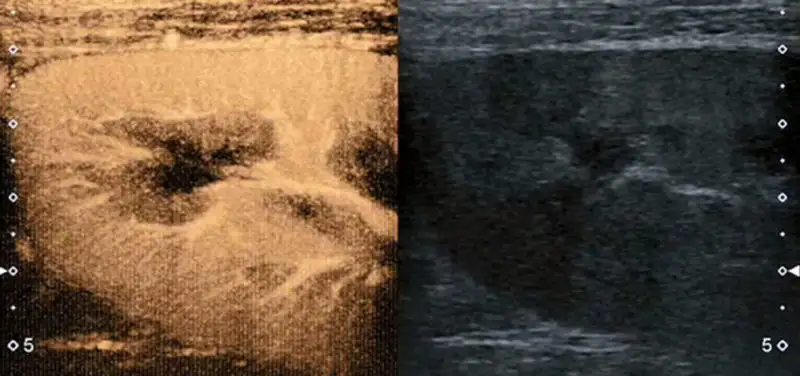

Image: This image demonstrates the blood flow to the upper pole of a kidney. The image on the right is the usual gray-scale ultrasound image of the kidney, whereas the image on the left is contrast-enhanced, showing the vessels and the perfusion of the renal tissue.

Ultrasound contrast is composed of tiny gas-filled microspheres or bubbles that reflect the sonographic sound waves. These bubbles are smaller in size than a red blood cell, and easily travel through the bloodstream. They last approximately five minutes in the body before they burst. The bubble’s outer shell, made up of a lipoprotein, is filtered from the blood by the liver, where it gets broken down and eliminated. The gas portion of the bubble is filtered and eliminated by the lungs. This five-minute lifespan allows for multiple contrast injections if necessary.

Special contrast-specific software on our ultrasound machines will enable us to obtain superb images of these tiny bubbles moving throughout the body, aiding in our diagnostic abilities. Short three-minute movies, or cine clips, as well as still images can be saved and later reviewed by the radiologist.